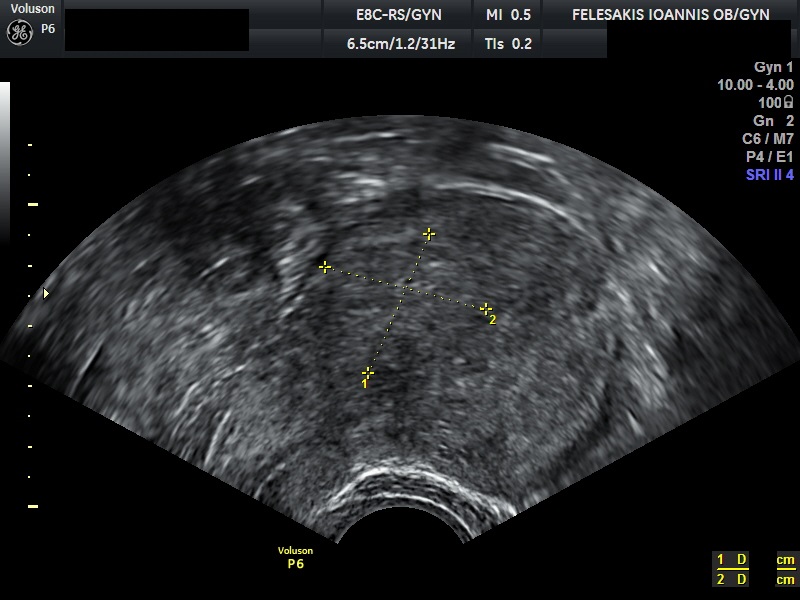

Τα συνηθέστερα συμπτώματα των γυναικών είναι η δυσμηνόρροια, η μηνορραγία και ο πόνος κατά την επαφή (δυσπαρεύνια). Σημαντικό είναι να τονιστεί, ότι η αδενομύωση δεν οδηγείται σε εξαλλαγή σε καρκίνο. Η διάγνωση της αδενομύωσης είναι δύσκολη, καθώς η υπερηχογραφική της εικόνα, πολλές φορές ομοιάζει με αυτή των ινομυωμάτων. Τη λύση έχει δώσει η Μαγνητική Τομογραφία (MRI) η οποία και βοηθάει στη διαφορική διάγνωση της υποκείμενης πάθησης.